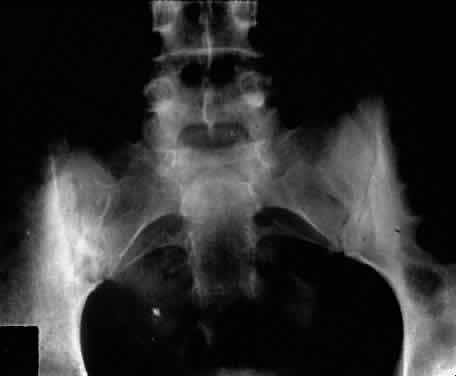

The associated arthritis and iridocyclitis, however, are similar in both conditions. Peripheral arthritis is seen in approximately 12% of patients with ulcerative colitis and approximately 20% of patients with regional enteritis. Radiographic evidence of sacroiliitis has been reported to show an incidence of approximately 18% and to be equal in both sexes in both conditions. Clinical spondylitis is seen in association with bowel inflammation in 4% to 7% of these conditions. The overall incidence of HLA-B27 in these two conditions may be slightly elevated, but is similar to that in the normal population. HLA-B27 is present in 53% to 75% of patients who have both spondylitis and inflammatory bowel disease. The sacroiliac involvement is frequently asymmetric (Fig. 5). It is not clear whether the spondylitis is secondary to the inflammatory bowel disease or to an overlap of the conditions. Spondylitis occurs before the bowel disease in 25% of patients, and there seems to be little correlation in the activity of symptoms between the sacroiliitis and the bowel disease. Colectomy does not affect the sacroiliitis, even when the bowel disease is improved. This is in contrast to the activity of the peripheral arthritis, which does seem to parallel the activity of the inflammatory bowel disease in 60% to 74% of patients. The peripheral arthritis also precedes the bowel disease in 7% to 11% of patients.33,36,37 It is not clear how these relate to the associated iridocyclitis.

Fig. 5. Asymmetric sacroiliitis with sclerosis and narrowing of right sacroiliac joint in a 22-year-old woman with inflammatory bowel disease and iridocyclitis.